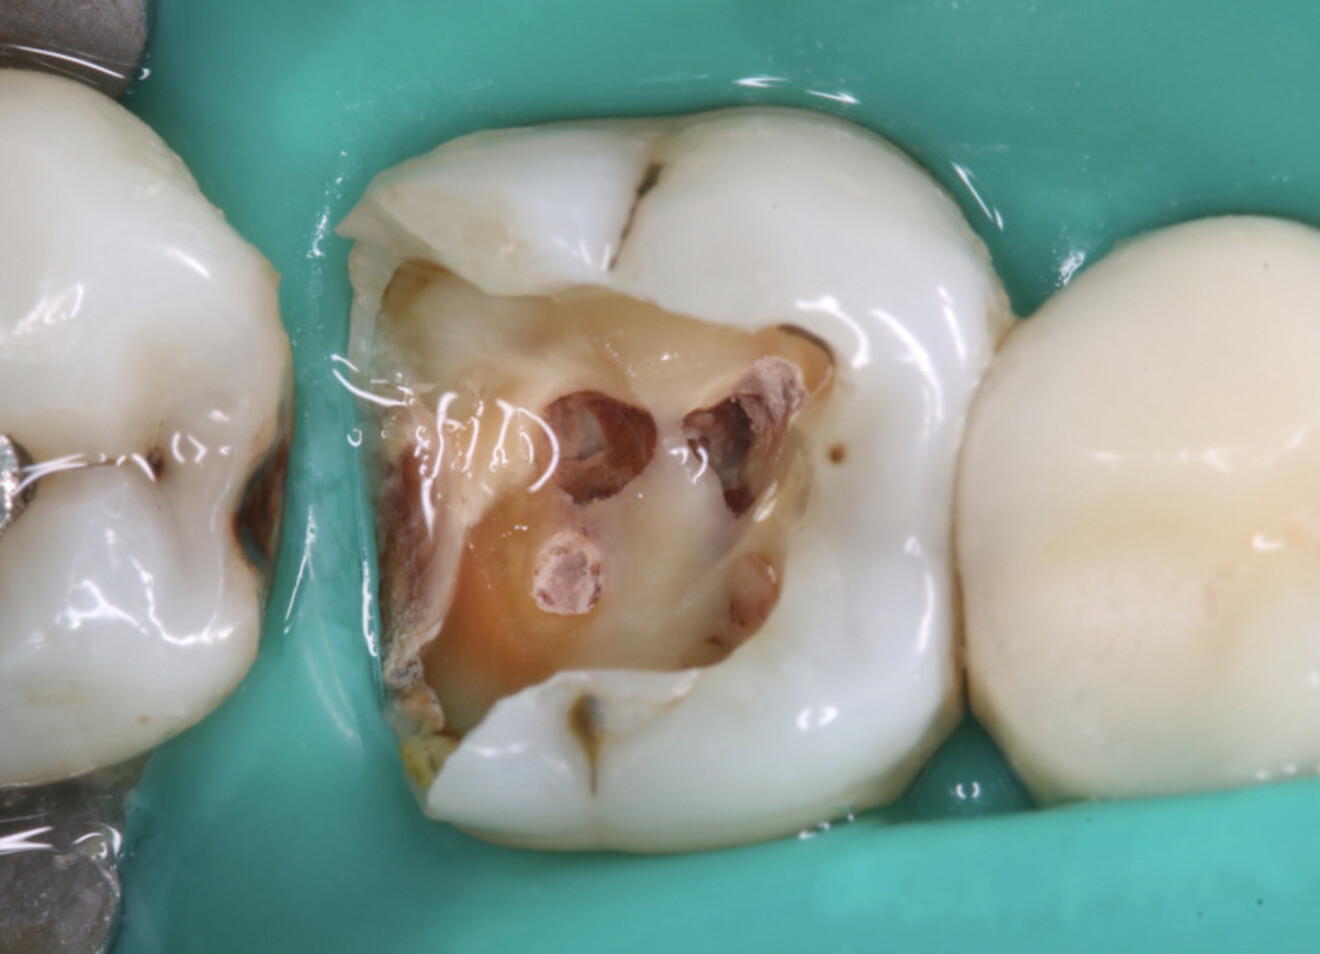

Il est important d’informer les patients de cette possibilité de sauver leurs dents même gravement endommagées et du pronostic du traitement par rapport à un implant. Bien que les implants soient très fiables, ils ne sont pas sans risque de complications. Lorsqu’ils sont bien informés, les patients choisissent souvent de conserver leurs dents naturelles.7 Aujourd’hui, les meilleures connaissances cliniques, la disponibilité de matériaux biocéramiques pour la réparation des lésions d’origine iatrogène et des défauts anatomiques, ainsi que l’utilisation généralisée du microscope opératoire, ont considérablement amélioré la prédictibilité de ces traitements.8, 9 Dès que la décision a été prise d’entreprendre le retraitement orthograde d’une dent et que toute restauration directe ou indirecte existante a été éliminée, la repréparation de la cavité d’accès est donc l’étape critique suivante. Il ne s’agit pas de créer un nouvel accès, mais plutôt de mieux délimiter l’accès existant afin d’optimiser l’entrée dans le système canalaire. Le champ opératoire doit être isolé à l’aide d’une digue en caoutchouc le plus tôt possible, de préférence immédiatement après le retrait de l’ancienne restauration. Notamment, toutes les procédures réalisées sous l’isolation d’une digue en caoutchouc sont associées à une production minimale de microgouttelettes salivaires.

Une intervention chirurgicale parodontale est parfois nécessaire pour rétablir la relation appropriée entre la structure dentaire restante, l’attache épithéliale et conjonctive, afin de reconstituer l’espace biologique. D’autres cas nécessitent une restauration préalable au traitement endodontique pour garantir une isolation adéquate des dents et une irrigation suffisante pendant l’intervention. Dans la mesure du possible, cette restauration doit être définitive et réalisée à l’aide de techniques adhésives appropriées, qui permettront l’obtention d’une base fiable pour la phase prothétique finale. Cette approche représente un gain de temps clinique et facilite un flux de travail plus ergonomique.